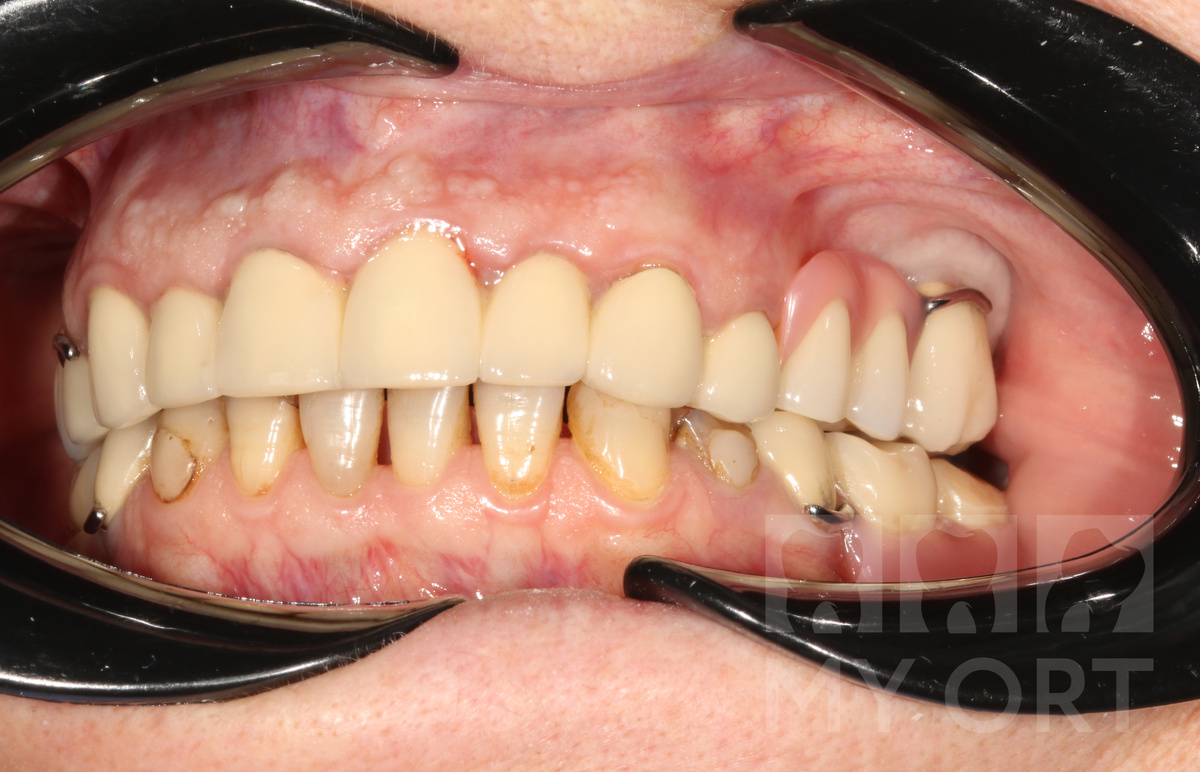

СитуацияДО. Вид спереди

Ситуация ДО. Вид сбоку

Пациентка обратилась с жалобами на болевые ощущения и кровоточивость мягких тканей после недавнего протезирования передних зубов верхней челюсти.

Пациентка носит частично-съемные протезы на обоих челюстях.

Фронтальные зубы у нее свои. Но нуждаются в лечении и дальнейшем протезировании для защиты.

3 месяца назад бабуля собралась с духом и средствами и заняла верхним рядом зубов. Ей был установлен несъемный мостовидный протез из металлокерамики от 4 до 4 зуба.